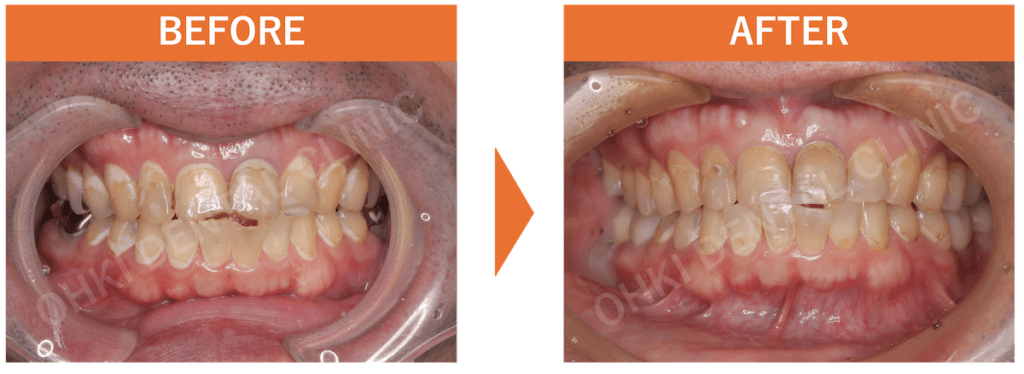

Before / After の比較:

治療前と比べて、上の前歯の正中離開(スキッパ)は改善されました。

仕上がりの特徴

- インプラントを埋入したことにより、噛む機能が回復したことが大きな結果です。

- 噛み合わせの柱が再建されたことで、今後、残存している歯の破折リスクや負担が軽減されました。

- 歯が抜けたままの状態ではなく、天然歯に似た形態でセラミック素材の上部構造を作製したため、見た目(審美面)も改善し、歯が再生したような状態を実現できました。